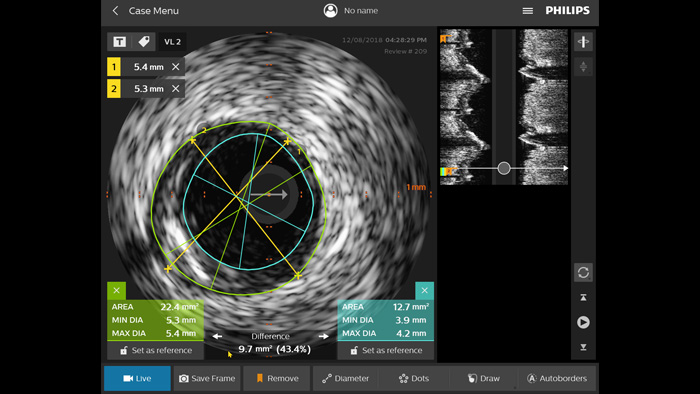

Optimice los resultados de los pacientes mediante un criterio estandarizado de EIV. 1,2 En comparación con la ICP guiada por angiografía sola, en todos los pacientes, ULTIMATE muestra que la ICP guiada por EIV reduce, de forma significativa, la revascularización de la lesión diana (RLD) impulsada clínicamente. Este beneficio se mantuvo durante tres años. Solo el 1,6 % de fallo en el vaso diana (FVD)* a los 12 meses y el 4,2 % de FVD a los 3 años cuando se cumplieron los criterios óptimos de la ICP guiada por EIV.